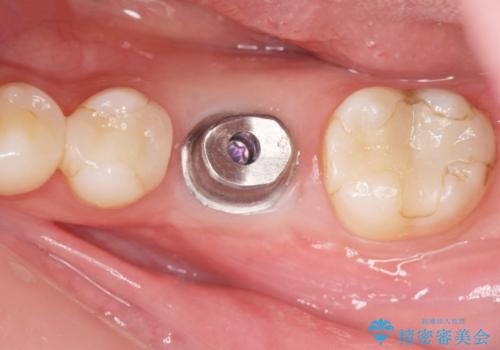

欠損部のインプラント補綴

- 失った奥歯にインプラント治療を受けたい、と希望され来院されました。

前後の歯を削らずに機能回復できるインプラントを用いて審美生、咬合機能の回復を計画します。

- 44万円(インプラント・チタンカスタムアバットメント・ジルコニアクラウン・仮歯)費用は治療当時の料金となります

痛みや腫れもほとんどなくインプラント治療を終えられ、しっかり噛むことができるようになった。と治療結果に満足いただくことができました。